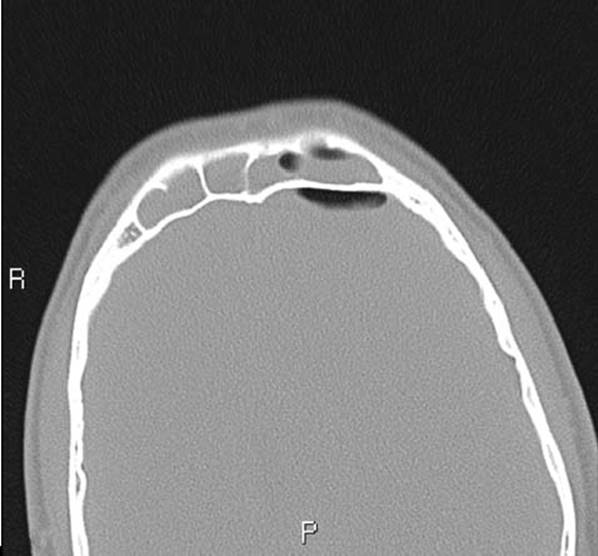

Intracranial complications are less frequent than orbital complications and are seen more with frontal or sphenoidal sinusitis. Intracranial spread of the infection should be suspected when a change in neurological or mental status is evident. Other symptoms and signs are high fever, severe headache, nausea and vomiting, seizures and signs of increased intracranial pressure. Neurological and/or neurosurgical consultation is warranted in case a patient with sinusitis develops one of the above issues. Intracranial complications include meningitis, epidural abscess, subdural empyema (Figs. 8.5 and 8.6A, B), and brain abscess. Frontal sinusitis may spread to the sinus bony walls and result in an osteomyelitis of the anterior and/or posterior tables. This may result in a frontal bone SPA and forehead cellulitis (Pott's puffy tumor).25

Figure 8.5 Computed tomography axial scan of frontal sinusitis with subdural empyema.